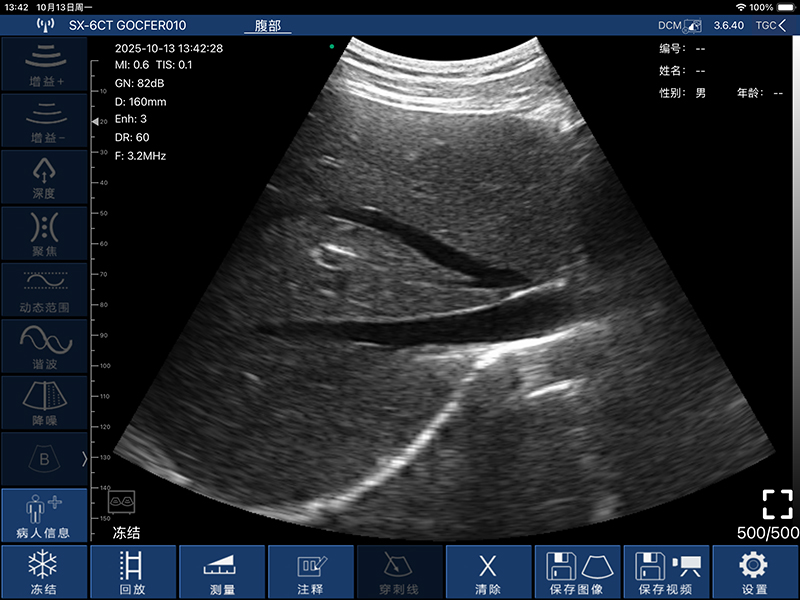

• 频率:凸阵探头3.2MHz/5.0MHz,阵探头7.5MHz/10.0MHz,相控阵探头2.5MHz/5.0MHz

• 深度:凸阵探头90/160/220/305mm,线阵探头20/40/60/80mm,相控阵探头90/120/140/160MM

• 扫描角度和宽度:凸阵探头60°,相控阵探头80°,线阵探头40mm

• 显示模式:B、B/M、Color、PDI、PW

• 图像调整:增益、动态范围、焦点、深度、谐波、降噪